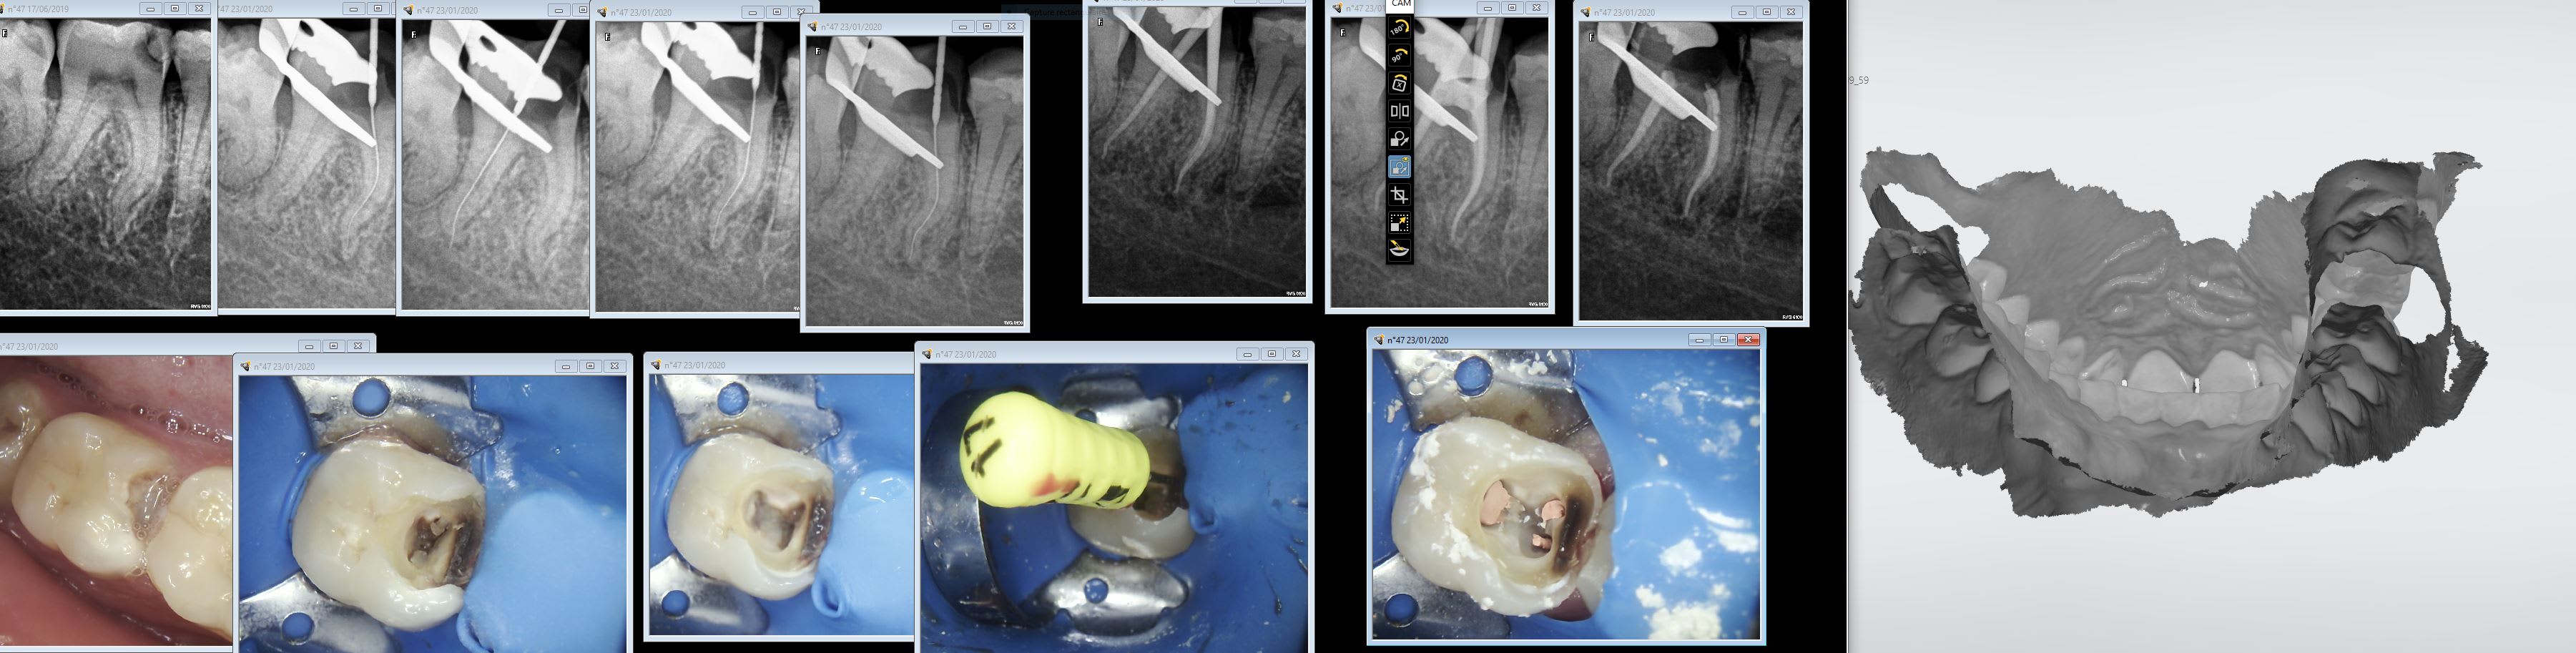

Oui des empreintes turbo. Préprep le temps que l'anesthésie de de 27 et 47 prennent pour les endos. Pour l'empreinte des préparations c'est 15 secondes. -))))

Miam ! Il y a encore de la marge d'efficience sur l'endo. L'obturation conventionnelle à mi canal au lentulo dans la salive.

Chicot , il agit un peu comme un écran de fumée .. dès que ça va pas dans le sens du vent du forum, hop , il te balance ses endo , photos sur 2 , 3 , 4 messages .. et voilà , le tour est joué , tu n'y vois plus rien .. Enfumé , tu es ... tu perds le fil , et les expressions de convictions un peu différentes de la pensée eugenolienne se dissipent . Certains utilisent les bombes lacrymogène , là ,il utilise ses captures d'écran !